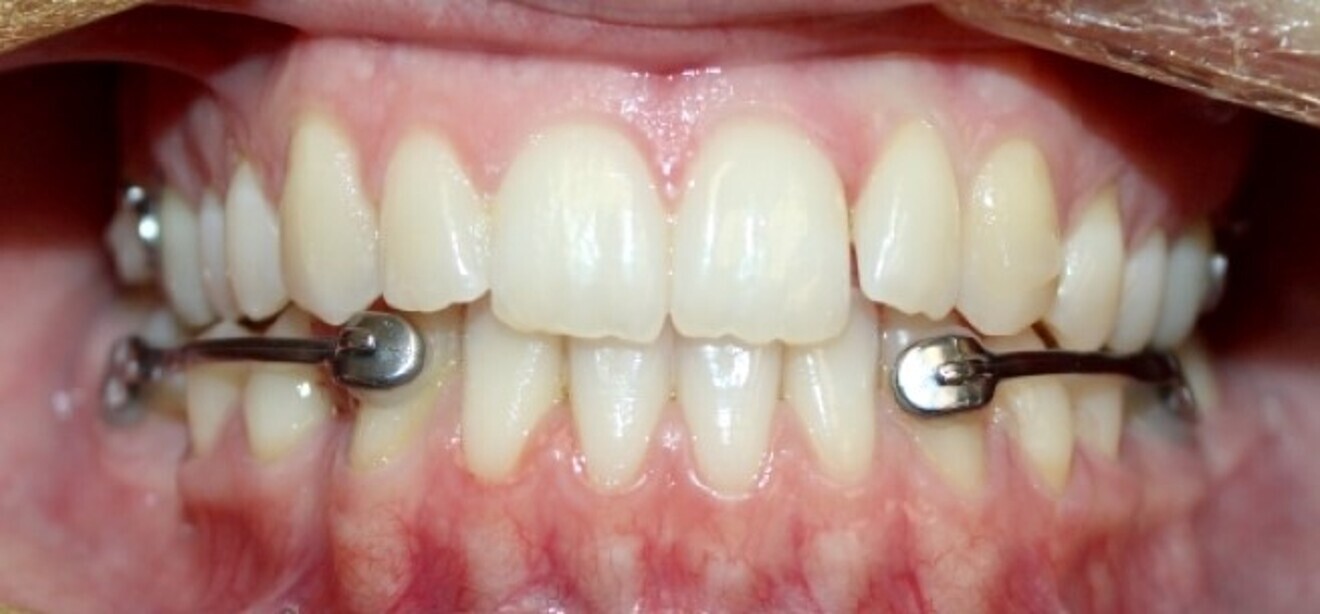

Aligners alone will fail because there are often significant skeletal components to Class III malocclusion, along with dental compensations, frequently making Class III a very difficult malocclusion to address with aligners alone. Instead use fixed Class III correctors off mandibular canines or first premolars, extending back to mandibular first molars or second molars, for a more assured, fast and profound Class III correction as the maxillary arch is aligning with clear aligners. An example of such a device is the Carriere Motion 3D Class III appliance (Figs. 20–22). The outcome is Class III correction that is much more predictable than with clear aligners alone.

Fig. 20a: Class III malocclusion requiring fixed appliance treatment. (a) Frontal view. (b) Occlusal view.

Fig. 20b: Class III malocclusion requiring fixed appliance treatment. (a) Frontal view. (b) Occlusal view.

Fig. 21: Carriere Motion Class III appliance in place.